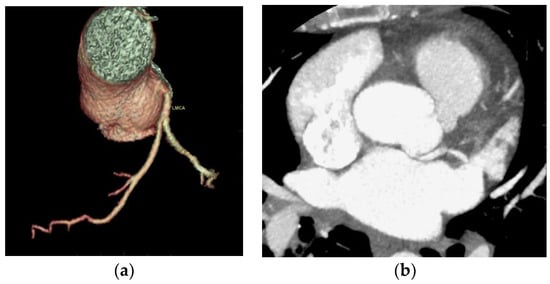

One case of right coronary anomaly originating from the left coronary sinus was found, with an anomalous course between the left pulmonary artery and the aorta, according to Figure 2.

One case of CAA with a right coronary anomaly originating from the left coronary sinus and an anomalous course between the pulmonary artery and the aorta was detected; a dynamic compressive effect could not be excluded at this level. According to the anatomical classification of the CAA of Angelini, there are several possible routes for the anomalous location of the coronary ostium at improper aortic sinus: in the posterior atrioventricular groove, retroaortic, between the aorta and the pulmonary artery, intraseptal, anterior to the pulmonary flow, in the posteroanterior interventricular groove [8]. The CAA with a route between the aorta and the pulmonary artery is considered the highest-risk route and is associated with an increased risk of sudden death. Young people are the most vulnerable to sudden death; the risk decreases for middle-aged and elderly people [5,21,22]. One hypothesis for why this effect occurs is that, during exercise, the aortic root and the pulmonary trunk expand and compress the coronary that passes between them. Another hypothesis is that the course of the coronary artery is partially embedded in the aortic wall and is laterally compressed during exertion [5,22,23].

Figure 2. Anomaly of the origin of the right coronary from the left anterior coronary sinus, with a course between the pulmonary artery and the aorta. (a) CCTA volume rendered cardiac transparency images showing anomaly of origin and course; the right coronary anomaly originates from the left coronary sinus with an anomalous course between the left pulmonary artery and the aorta. Normal origin of the left main coronary artery from the posterior portion of the left coronary sinus with a normal trajectory. Intermediate filiform branch is present; (b) CCTA axial contrast-enhanced image at the aortic root showing anomaly of the origin and course; the right coronary abnormally originates from the left coronary sinus; (c) CCTA axial contrast-enhanced image at the aortic root showing RCA with an anomalous course between the pulmonary artery and the aorta; (d) CCTA curved planar reformatted image of the RCA; (e) CCTA curved planar reformatted image of the RCA origin; (f) CCTA vessel cross-section image of the RCA with an anomalous course between the pulmonary artery and the aorta.